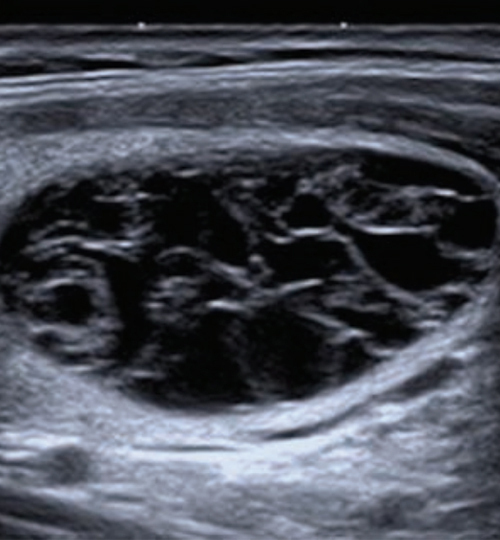

* Le score échographique de risque European-Thyroid Imaging Reporting and Data System (EU-TIRADS) permet de prédire le risque de malignité à partir de l’aspect échographique :

– score 2 : bénin (kystes simples, nodules spongiformes) ;

Figure : Nodule spongiforme. Échographie en coupes longitudinale et transversale d’un nodule EU-TIRADS 2. Extrait de : Russ G. Prise en charge du nodule thyroïdien. Rev Prat 2017;67(6);663-7